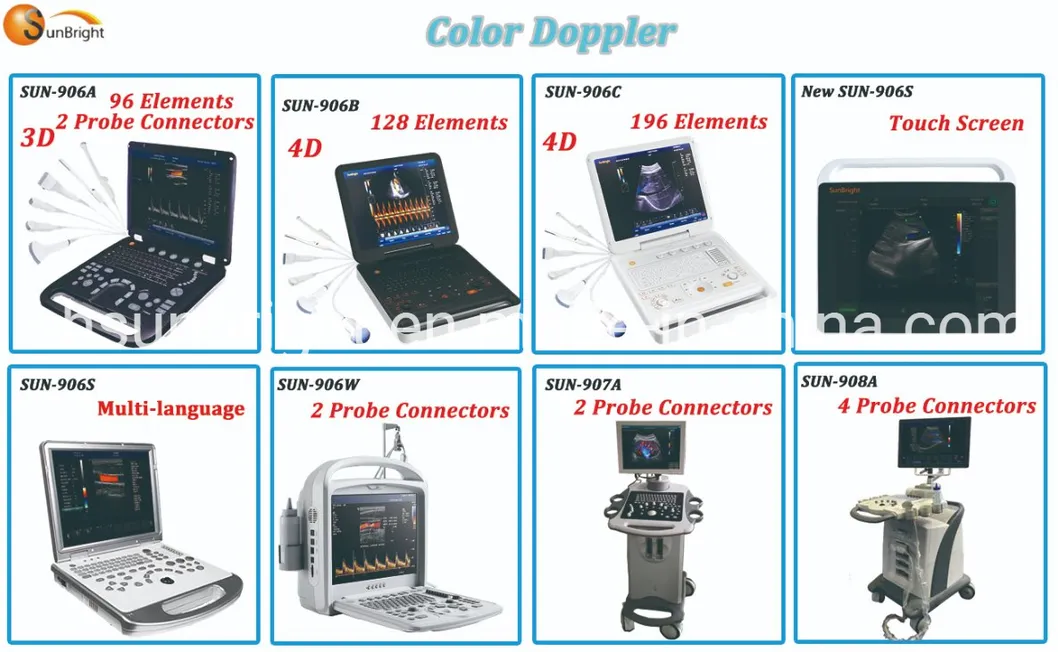

3D Full Digital 4D Veterinary Medical Best Equipment with Convex Probe

3d full digital 4d veterinary medical best equipment with convex probe

Imaging Modes

B, 2B, 4B, M, B/M, B/C, B/D, B/C/D, B/CFM/D, PDI Color, Dual Color,

2D 3D 4DColor Compound, PW, CW, Duplex/Triplex, CFM, CDE, Directional PD, CD